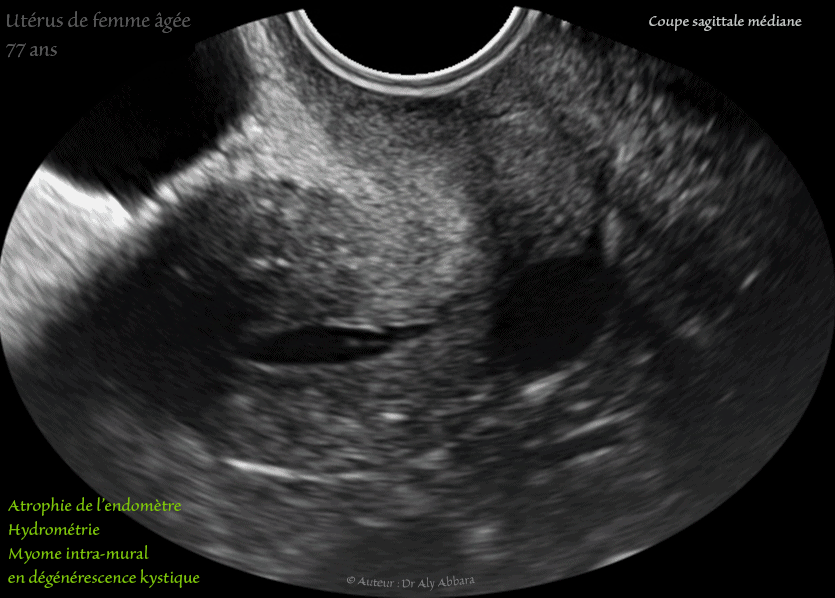

Utérus d'une femme âgée de 77 ans - hydrométrie - atrophie de l'endomètre - myome en dégénérescence kystique

Images échographiques animées montrant l'utérus d'une femme âgée de de 77 ans, avec plusieurs éléments anatomiques liés au vieillissement (sénilité)

I- Hydrométrie :

Il s'agit d'une rétention des sécrétions endométriales dans la cavité utérine liée à la sténose, voire l'obstruction totale du canal cervical.

II- Atrophie de l'endomètre :

Elle est la conséquence de l'effondrement du taux des estrogènes par l'inactivité de la fonction hormonale ovarienne.

III- Myome utérin intramural type 4 (de classification FIGO) en dégénérescence kystique